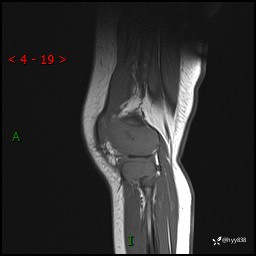

现病史:患儿1月前无明显诱因出现左下肢跛行,伴左膝关节红肿,无发热、咳嗽、恶心、呕吐等症,于当地医院就诊行X线片未提示异常,今至我院门诊就诊,门诊医师拟“跛行待查”收入院。 病后,患儿精神、食欲可,睡眠欠安,大小便通畅,体力体重无明显下降。

左膝MRI平扫